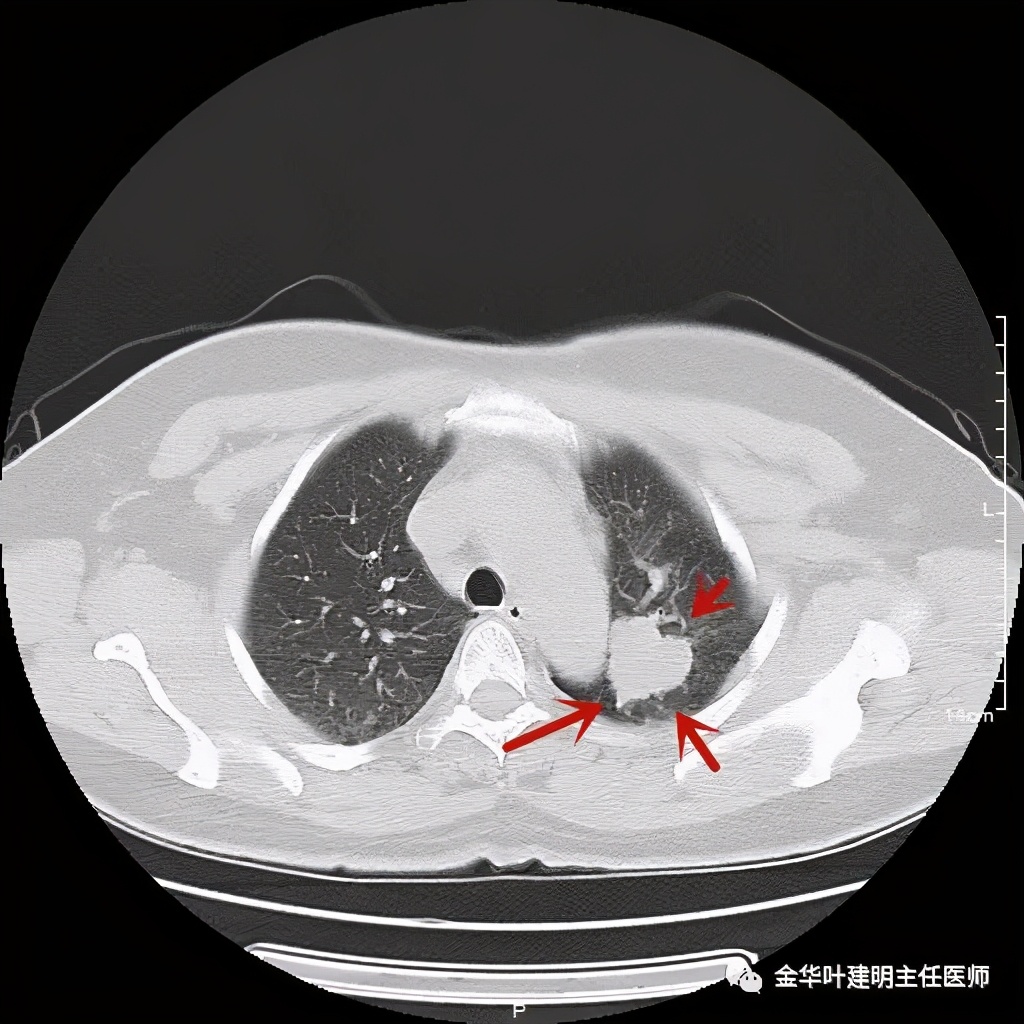

六、神经内分泌癌(此例为不典型类癌,小细胞癌以后再总结):

影像特征:不典型类癌一般圆形生长,实性,边缘比较光滑,但硬度不够。侵蚀力也不够。就像这例,我们发现其与肺动脉接触的地方,居然无法推压血管,反而肿瘤被血管占据了其生长的位置,在支气管内,肿瘤也是对支气管壁没有造成明显的破坏。也就是说 圆形边清较软、侵蚀力弱的实性结节 要考虑类癌的可能性。